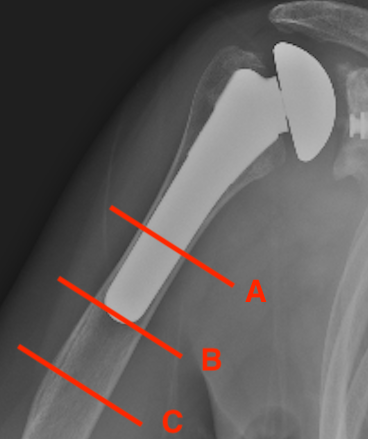

Peri-prosthetic Fracture

Cause

1.  Trauma

2.  Atraumatic - stress riser / loosening

Wright and Cofield Classification

Cofield Classfication

A:  Fracture centred at the tip and extends proximally greater than 1/3

B:  Fracture at tip only

C:  Fracture distal to tip of the prosthesis and extends into distal metaphysis

Options Humeral Shaft Fracture

A.  Non operative Management

- well-fixed prosthesis

- acceptable alignment

TSR Periprosthetic FractureTSR Periprosthetic Fracture

B.  ORIF

- displaced tuberosity fractures

- well-fixed prosthesis and fracture distal to prosthesis

Anterolateral approach and plate

C.  Revision

- loose humeral prosthesis / osteolysis

Long stem > 2 cortical diameters past fracture

aTSA fracture 1aTSA fracture 2revTSA following fracturerevTSA for fracture

Results

Kumar et al JBJS Am 2004

- 11 / 16 patients with periprosthetic humeral fractures treated nonoperatively

- 6 healed after 180 days of non operative treatment

- 5 required operation after 123 days for non union

- recommended all fractures can be treated nonoperatively if well aligned and prosthesis stable

- if not united by 3 months, recommend intervention